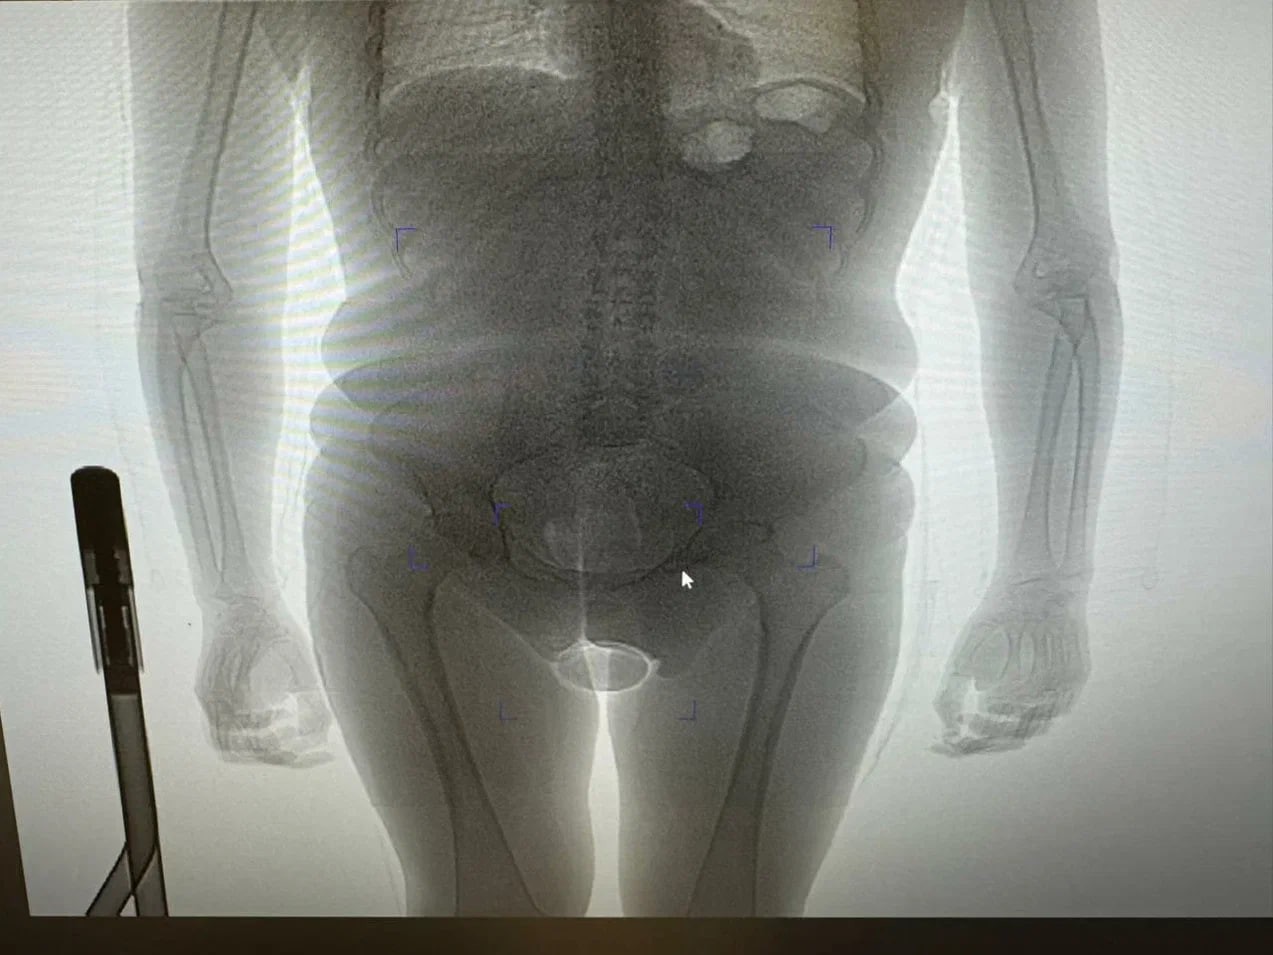

В ходе досмотра таможенники обнаружили два презерватива с порошкообразным веществом. Один был спрятан в нижнем белье пассажирки, а второй — в естественном отверстии. Обнаружить его помог рентген.